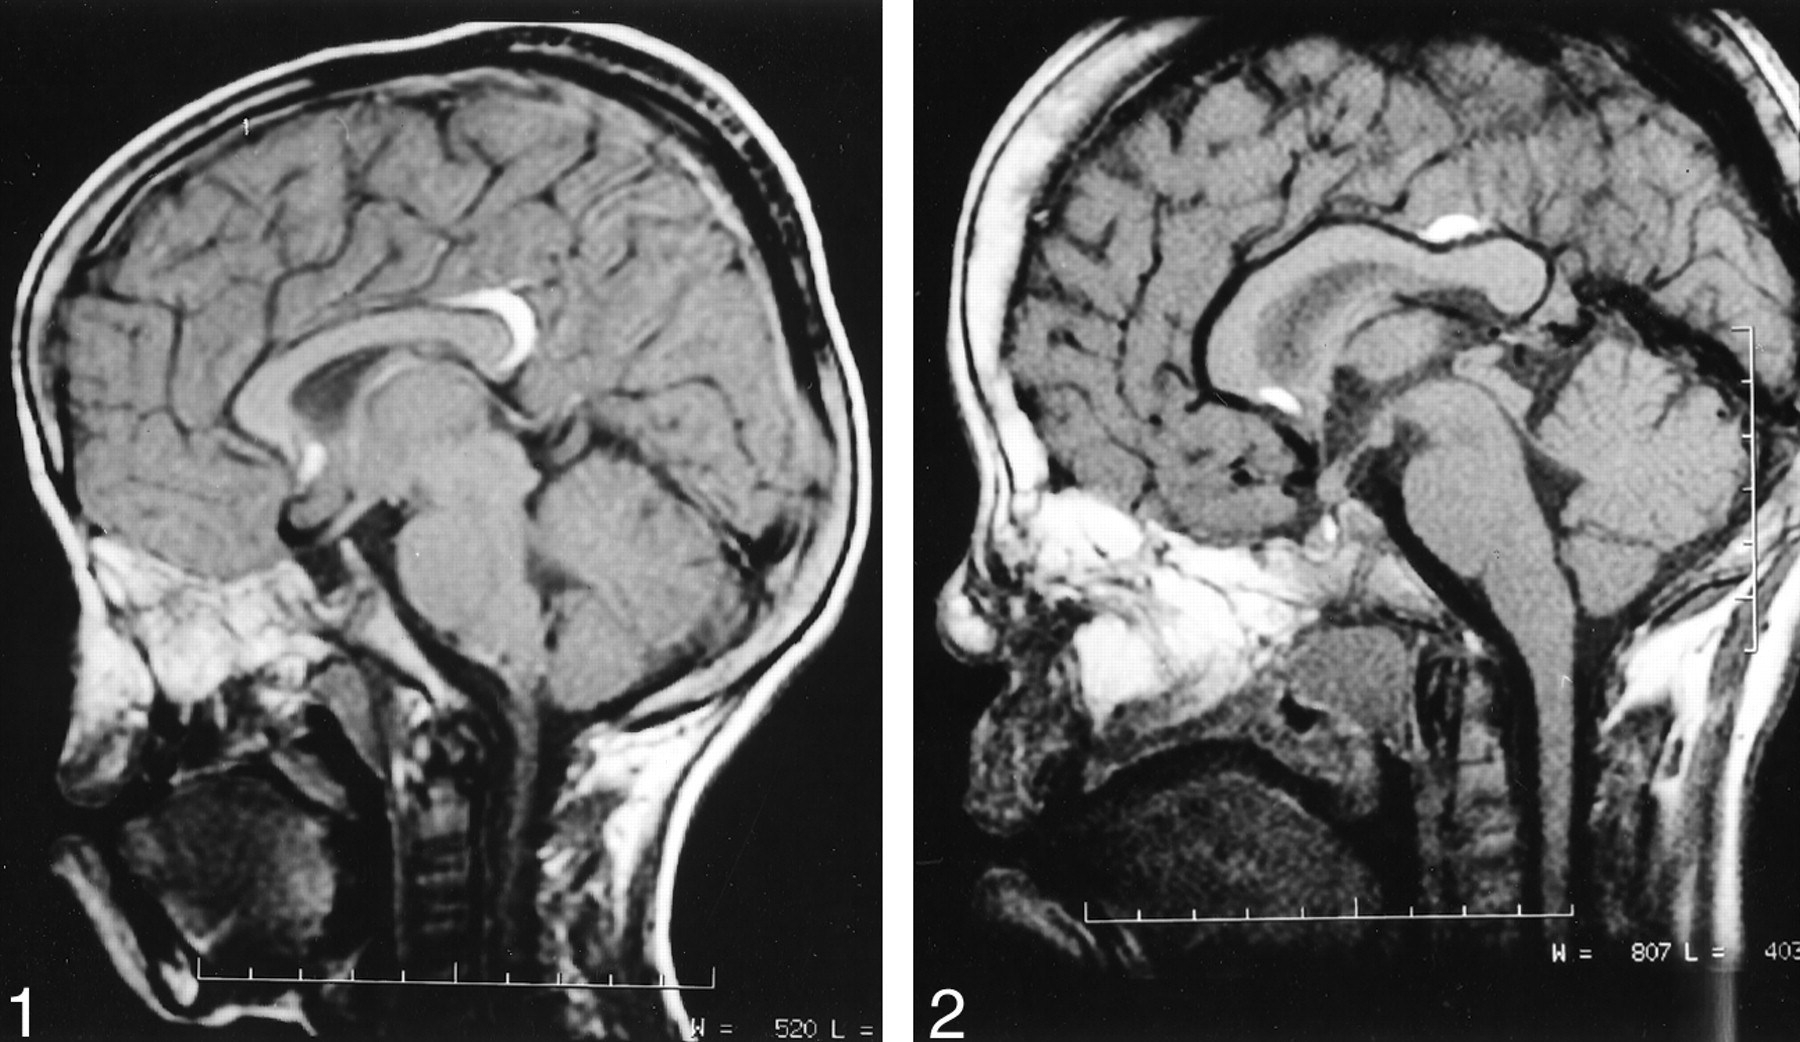

A 12-year-old girl with hypertelorism and congenital craniofacial deformities in the form of a median cleft affecting the palate, lip, and nose presented to our hospital for surgical correction. The mother’s pregnancy and delivery were uneventful. The patient’s intelligence was normal. The patient had no history of seizures or headache. CT scans of the facial bones showed hypertelorism, a depressed and bifid nasal bridge, and depression of the floor of the anterior cranial fossa. Findings from a skeletal survey were unremarkable. MR imaging revealed two pericallosal lipomas, one in relation to the rostrum and the other in relation to the splenium; these measured 0.8 and 1.9 cm in maximum diameter in the axial plane (Fig 1). The corpus callosum was well developed.

Case 1. Midsagittal T1-weighted MR image (TR/TE/NEX, 550/20/1.5) of the brain shows two small curvilinear pericallosal lipomas, one in relation to the rostrum and the other in relation splenium of corpus callosum. The corpus callosum is well developed. The deformity in the nasal region is depicted.